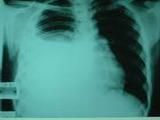

砷肺癌(lung cancers caused by arsenic compounds )是指砷所致肺癌。 砷及其化合物經呼吸道進人少、體所引起的惡性肺腫瘤砷及其化合物長期以來就被認為是人類可疑致癌物。1922年以後大量的流行病學資料證實砷除致皮膚癌之外,還致肺癌接觸砷的作業有 殺蟲劑製造工業及殺蟲劑噴霧,銅、鎳、鑽的冶煉和三氧化二砷礦石的開採等 病理砷肺癌病理以鱗狀上皮細胞癌最多,其次為未分化癌、腺癌和混合癌。發病部位以中心型居多,外周型次之。

砷也可能是在某種原 發性致癌物造成脫氧核糖核酸(DNA)損傷的情況下,妨礙修復,因此,砷是一種輔助致癌物診斷砷肺癌的診斷應根據接觸砷的職業史結合臨床和病理檢查綜合判定潛伏期多數發病率和死亡率從4歲開始上升·對砷中毒患者和發現癌前病變戴其他早期癌瘤指征者,應定期檢查,及時確診。